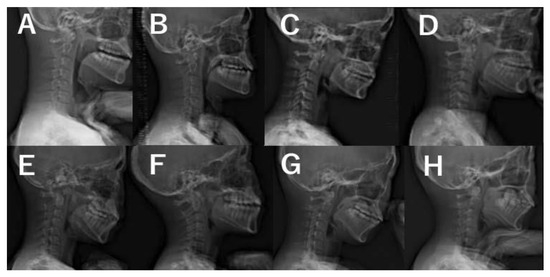

2. Materials and Methods

3. Results

3.3. Radiographic Evaluations